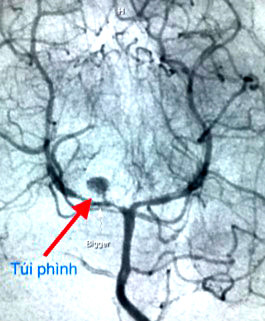

Mạch máu não bệnh nhi bị phình to, vỡ. Ảnh: Thanh Niên. |

Các bác sĩ nhận định bé có nguy cơ cao là do vỡ túi phình mạch máu não. Kết quả chụp mạch máu não xóa nền (DSA) để đánh giá cho thấy có túi phình ở động mạch não sau bên phải, túi phình này bể ra gây nên tình trạng xuất huyết.

Sau khi hội chẩn, các bác sĩ quyết định thực hiện can thiệp mạch. Tuy nhiên, vào ngày sau khảo sát lại các bác sĩ thấy túi phình to hơn kết quả khảo sát lần đầu vào có nguy cơ tái vỡ nếu không điều trị kịp thời.

Các bác sĩ đã dùng những ống thông, dây dẫn siêu nhỏ luồn vào mạch máu, tiếp cận được túi phình và bít tắc hoàn toàn túi phình bằng những vòng xoắn kim loại. Sau can thiệp, sức khỏe bé ổn định và phục hồi dần.